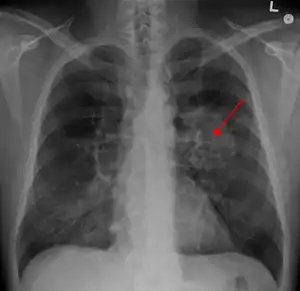

Performing a chest radiograph is one of the first investigative steps if a person reports symptoms that may be suggestive of lung cancer. This may reveal an obvious mass, the widening of the mediastinum (suggestive of spread to lymph nodes there), atelectasis (lung collapse), consolidation (pneumonia), or pleural effusion.[7] CT imaging of the chest may reveal a spiculated mass which is highly suggestive of lung cancer, and is also used to provide more information about the type and extent of disease. Bronchoscopic or CT-guided biopsy is often used to sample the tumor for histopathology.[17]

Lung cancer often appears as a solitary pulmonary nodule on a chest radiograph. However, the differential diagnosis is wide. Many other diseases can also give this appearance, including metastatic cancer, hamartomas, and infectious granulomas caused by tuberculosis, histoplasmosis or coccidioidomycosis.[66] Lung cancer can also be an incidental finding, as a solitary pulmonary nodule on a chest radiograph or CT scan done for an unrelated reason.[67] The definitive diagnosis of lung cancer is based on the histological examination of the suspicious tissue[1] in the context of the clinical and radiological features.[6]

The lungs are a common place for the spread of tumors from other parts of the body. Secondary cancers are classified by the site of origin; for example, breast cancer that has been spread to the lung is called metastatic breast cancer. Metastases often have a characteristic round appearance on chest radiograph.[76]